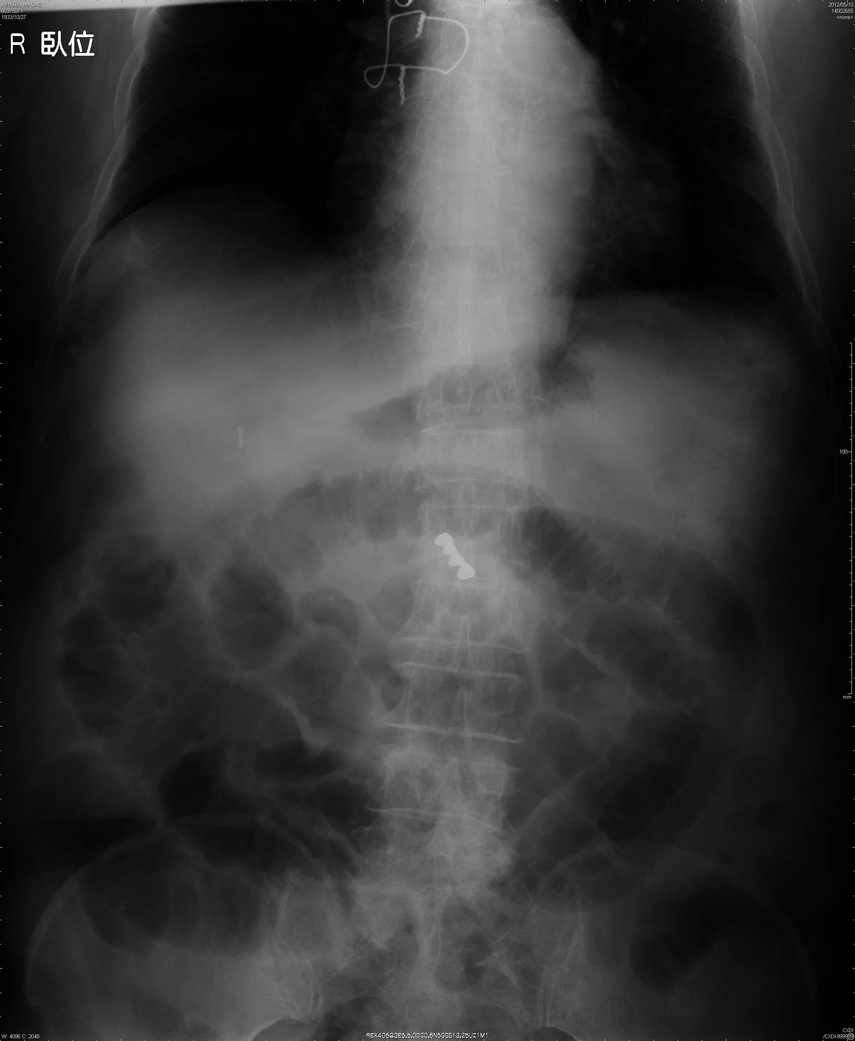

直腸異物(スプレー缶)例

a:直腸内に20cm×6cmのスプレー缶を認める、穿孔や腸閉塞の所見はなし。

b:同上

c:直腸周囲に炎症の波及が疑われた。